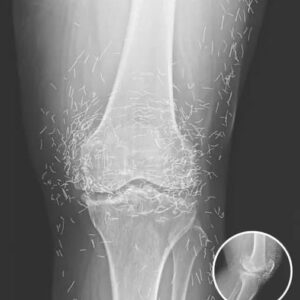

Doctors Stunned After Looking At This X-Ray Of Woman Suffering Joint Pain

Hidden Gold Discovered in Woman’s Knees After Routine X-Ray Doctors in South Korea were stunned after a routine knee X-ray on a 65-year-old woman revealed hundreds of…